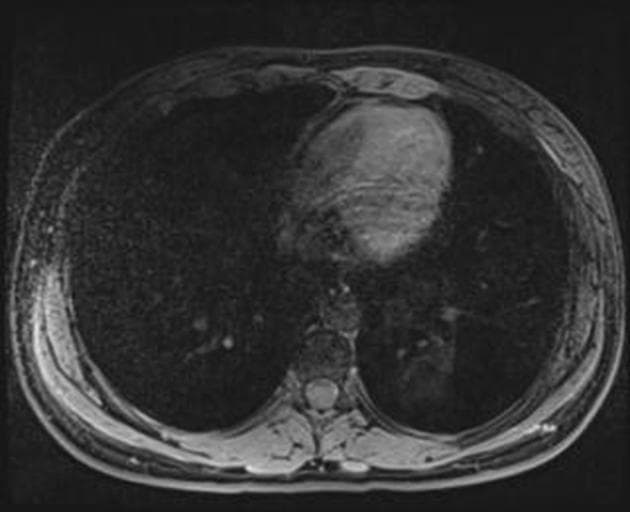

Coronal T2

MRI•Coronal T2•1 / 14

- Tổn thương dạng nốt tại mặt dưới thuỳ gan trái, có tín hiệu đồng tín hiệu so với nhu mô gan, trừ thì động mạch sau khi tiêm thuốc cản quang, khi đó tổn thương cho thấy ngấm thuốc thì động mạch.

- Có sẹo trung tâm nhỏ.

Trường hợp điển hình của tăng sản tuyến foca (focal nodular hyperplasia - FNH).

- "Đặc điểm hình ảnh điển hình bao gồm tổn thương ranh giới rõ, đồng tín hiệu trên hầu hết các chuỗi xạ hình, tăng ngấm mạnh ở thì động mạch và sẹo trung tâm tăng ngấm muộn."

Tăng sản tuyến foca (FNH) là tổn thương gan lành tính phổ biến thứ hai sau u máu, chủ yếu ảnh hưởng đến phụ nữ trẻ đến trung niên. Bệnh được cho là do phản ứng tăng sản tại chỗ trước một dị dạng mạch máu khu trú, thường xảy ra trên nền gan bình thường. Tổn thương thường xuất hiện như một khối ranh giới rõ, không có vỏ bao, với sẹo trung tâm hình sao đặc trưng và tăng ngấm thuốc đồng đều mạnh ở thì động mạch. Trên cộng hưởng từ, FNH cho hình ảnh giảm tín hiệu ở chuỗi T1, tăng tín hiệu ở chuỗi T2 so với nhu mô gan, và đồng tín hiệu ở thì chức năng gan do sự hiện diện của tế bào gan và ống mật nhỏ hoạt động. Sẹo trung tâm tăng ngấm thuốc ở thì muộn. Mặc dù FNH thường không triệu chứng và được phát hiện tình cờ, cần phân biệt với u tuyến tế bào gan và các tổn thương di căn tăng sinh mạch. Sinh thiết hiếm khi cần thiết nếu hình ảnh điển hình. Điều trị chủ yếu là theo dõi bảo tồn, không cần cắt bỏ trừ khi có nghi ngờ chẩn đoán hoặc bệnh nhân có triệu chứng.